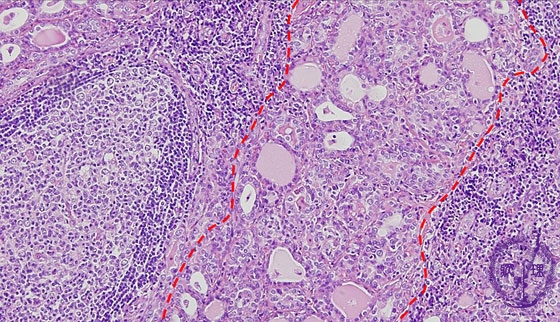

- ★(4)Chronic thyroiditis (Hashimoto disease)

Microscopic findings (HE stain, middle power view). Marked lymphocytic infiltrations, lymphoid follicles, atrophic thyroid follicles (dotted -line) with associated decreases of colloid material, are detected.